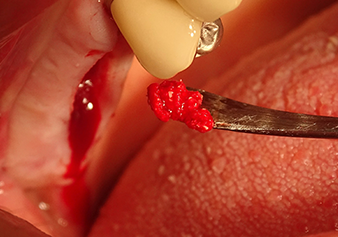

Après un contrôle intermédiaire (Fig. 4), une étape de préparation ultérieure est exécutée (Fig. 5). Puis on utilise l’insert Z35P hydraulique pour relever la membrane vers la position souhaitée (Fig. 6 et 7). Ensuite, une préparation piézochirurgicale supplémentaire est pratiquée sur le site implantaire, en utilisant pour terminer un burin rotatif et une fraise à épaulement jusqu’à 4,8 mm de diamètre d'implant. Avant l’insertion de l'implant, le matériau d’augmentation (taille de particules env. 0,8-1,6 mm) est introduit sous la membrane de Schneider (Fig. 8).